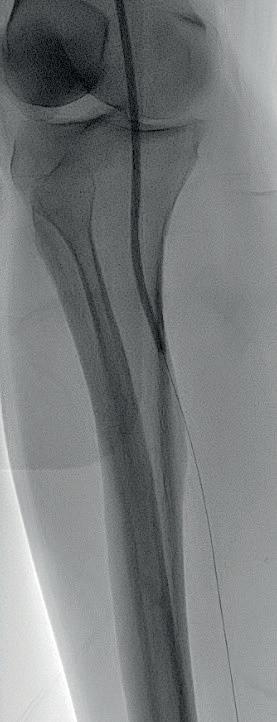

Diagnostic angiogram demonstrated a right popliteal occlusion extending into his proximal tibial vessels (Figure 1). An 0.014” wire was able to easily cross the lesion and pass into the posterior tibial vessel. Intravascular ultrasound (IVUS) demonstrated chronic intraluminal thrombus

with limited evidence of atherosclerosis (Figure 2). A 2.0mm Auryon laser catheter was used to perform a simultaneous athrectomy-thrombectomy (Figure 3). After a single pass, repeat angiogram demonstrated >70% luminal gain (Figure 4). Low pressure (2atm) balloon angioplasty was then performed (Figure 5). Completion angiogram (Figure 6) demonstrated no residual stenosis, with brisk flow into the posterior tibial vessel. The patient developed a palpable posterior tibial pulse, and, at six months, has no claudication symptoms.